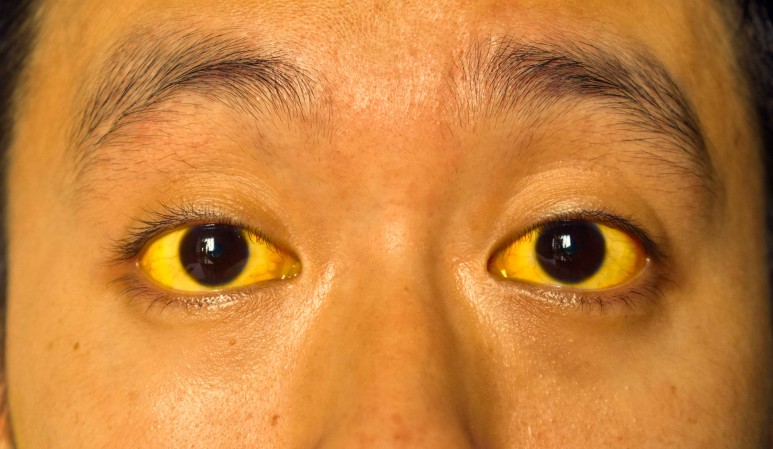

황달이 발생하는 원인은 사마자마입니다.

적혈구가 파괴되어 생기는 용혈성 황달도 있는데, 오늘은 담관 폐쇄로 인해 발생하는 용혈성 황달에 대해서 말씀드리겠습니다.

그 중 오늘은 폐쇄성 황달에 대해서 이야기를 해보도록 하겠습니다.

혈청 생화학적인 변화가 담관 폐쇄에서 발생하는 경우 혈청 빌리루빈 상승이 가장 중요합니다.담도계가 70% 이상 밀리면 상승하기 시작합니다. 그러나 폐쇄가 오래된 경우는 혈중 농도와 비례하여 신장에서 빌리루빈이 직접 배출되므로 수치가 최대 40mg/dL 이상으로 상승하지 않습니다.